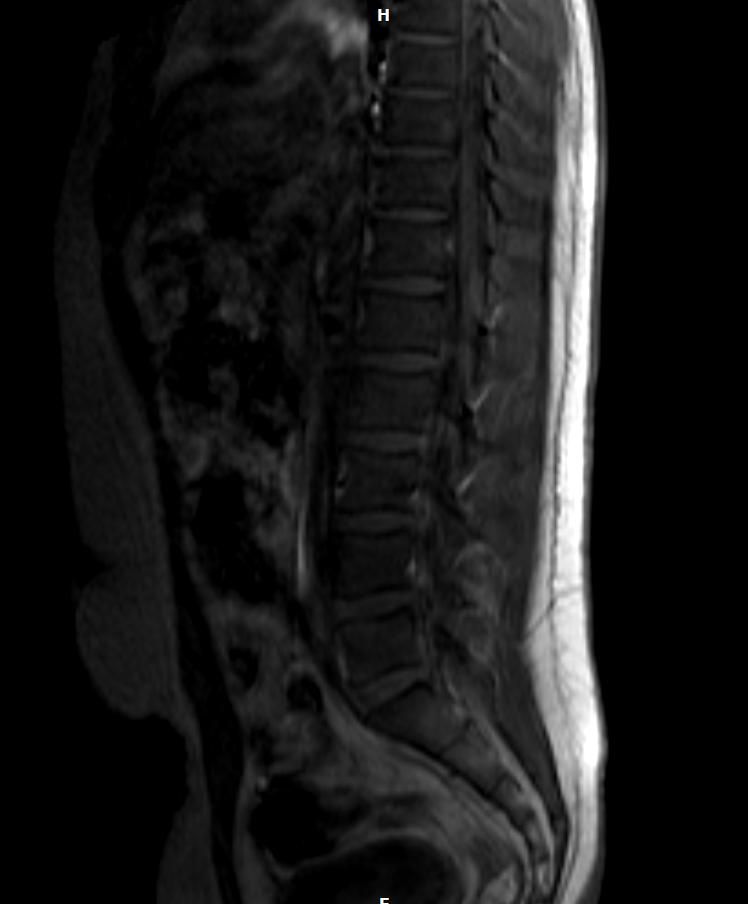

• 2번 째 사진

올려주신 MRI처럼 보이는 흰색 음영은 대부분 정상적인 체액이나 주변 연부조직, 혈관구조로 보이는 경우가 많습니다. 특히 척추 앞쪽이나 가운데 보이는 밝은 부분은 장기나 지방층, 체액 신호일수 있습니다. MRI는 단면을 보는 검사라 각도에 따라 평소 안보이던 구조가 강조되어 보일수 있습니다. 병원에서 골절아니고 심각하지 않다라고 했다면 급한 움ㄴ제일 가능성이 낮습니다. 암 같은 경우에는 보통 모양이 불규칙하거나 주변조직 침범 소견이 동반되는데 그런설명이 없었다면 가능성은 낮습니다. 지금단계에서는 과도한 걱정보다는 정식 판독 결과지를 확인하는것이 가장 정확합니다!

언급해주신 부위 주변의 음영은 골절 소견이 아니라면 큰 이상이 있거나 우려하시는 것과 같이 암과 같은 종양의 가능성은 낮을 것으로 생각됩니다.

척추 앞을 지나가는 대동맥과 같은 혈관 부위이거나 척추 앞쪽에 위치하는 인대와 같은 구조물일 수 있으며, 보다 정확한 소견은 주치의분이나 판독의분께 확인받으시는 것이 좋겠습니다.